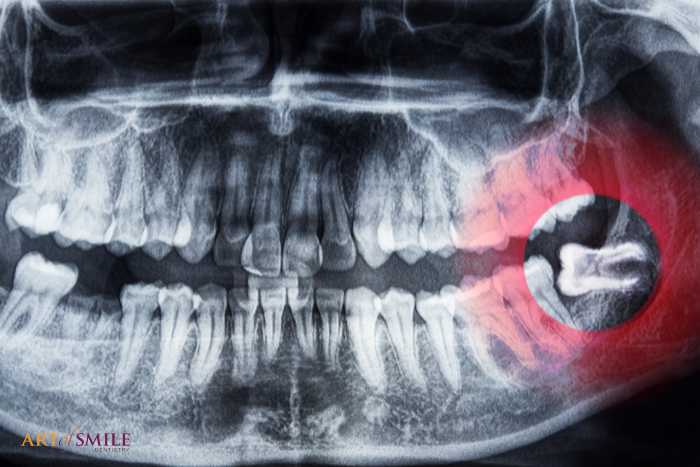

Wisdom teeth, or third molars, are the last set of teeth to develop. Sometimes these teeth emerge from the gum line and the jaw is large enough to allow room for them, but more often, they fail to emerge in proper alignment or do not fully emerge through the gum line and can create crowding, misalignment, infections, or cysts.